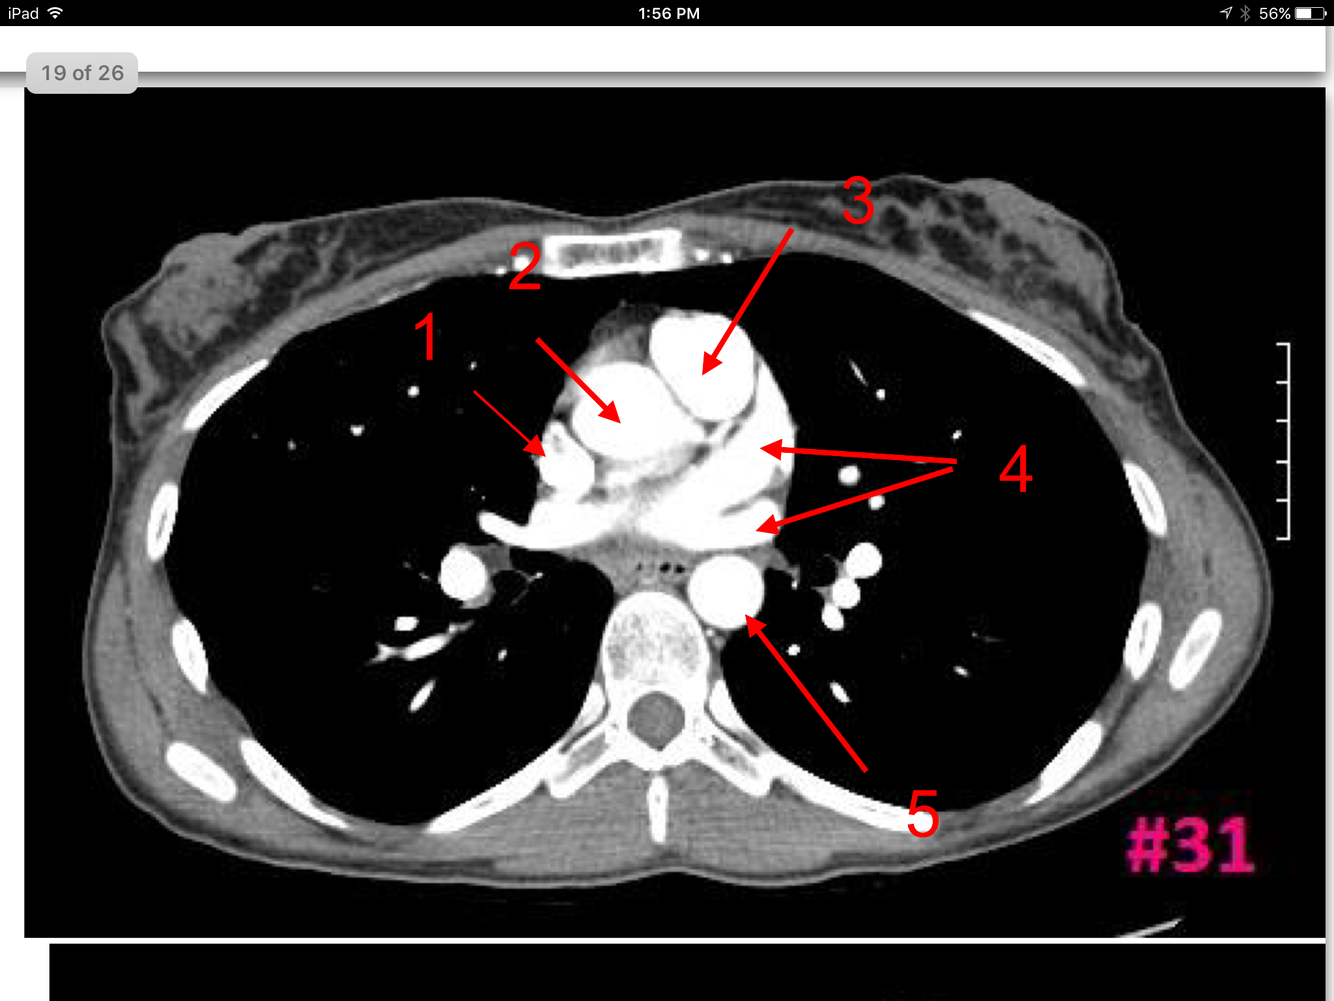

19

Q

Study These Flashcards

A

Lt superior and inferior pulmonary veins

Auricle of Rt atrium

Aortic sinus

Thoracic aorta

Lt atrium